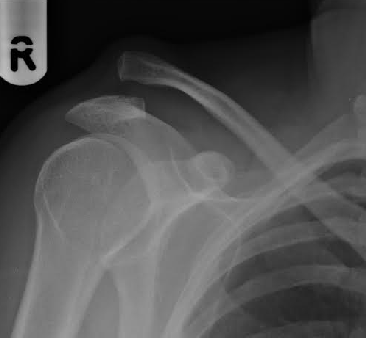

Chronic Reconstruction of the unstable ACJ

An incision is made over the top of your shoulder (see image of healed scar below) to expose your lateral clavicle and coracoid process. The medial part of your deltoid muscle is elevated and flipped off the lateral clavicle to allow exposure of the coracoid. A wafer of bone is resected from the damaged end of your clavicle and debris is cleared to allow the clavicle to be returned to its correct position. Very strong specially-woven Polyester rope (LARS ligament: see image below) is looped beneath the bony coracoid process of your shoulder blade and fixed through two holes in your collarbone with small screws. The remaining nylon rope is used to strengthen further the reconstruction. Sometimes a second implant (Internal Brace - a fibre-tape held with two suture anchors) is used to augment front-to-back stability.

Photograph of patient 5 months after surgery. Note the scar and the normal shoulder contour.  A photograph (From Corin website) of the LARS ligament used for the reonstruction of the coraco-clavicular ligaments

A pre-op and post-op image of a grade 5 AC separation reconstructed with LARS ligament.